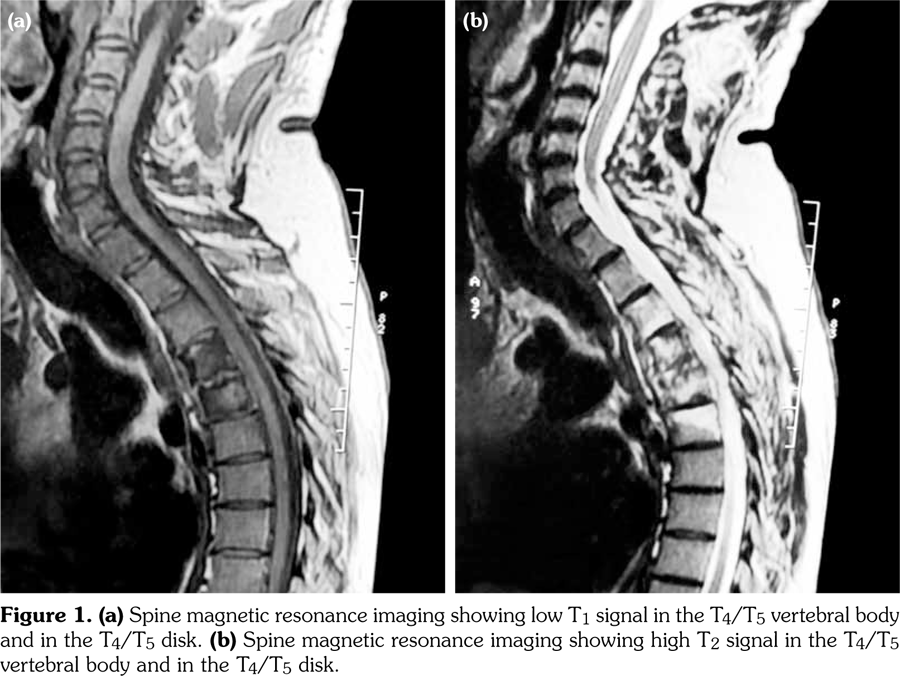

Laboratory examination revealed a slightly elevated C-reactive protein level (16 mg/L) and erythrocyte sedimentation rate (40 mm). Serum levels of calcium, albumin and phosphorus were within the normal range. Blood cell counts, liver tests, and renal function were unremarkable. Blood cultures, urinanalysis, tumor markers, and serodiagnosis for brucella were negative. Tuberculosis skin test was negative. Spine magnetic resonance imaging showed low T1, high T2 signal and contrast enhancement in the T4/T5 and L3 vertebral body and in the T4/T5 disk (Figure 1). Sacroiliac joints were normal. Computed tomography-guided biopsy of the T4/T5 disc demonstrated nonspecific inflammation and culture of this specimen was negative. Computed tomography scan of the sternoclavicular joints revealed hyperostosis and erosions involving the sternum as well as medial end of clavicle (Figure 2). Clavicular biopsy showed irregular sclerotic trabeculae. Human leukocyte antigen B27 typing was positive.

The most common site of skeletal involvement is the anterior chest wall (70-90%) followed by the spine, where abnormalities are found in approximately one-third of patients.(2) Vertebral involvement may manifest as vertebral body osteosclerosis, hyperostosis, paravertebral ossification, lesions at the discovertebral junction, and may lead to vertebral collapse as described in our patient.(2) In about 15% of cases, the enthesophytes are limited to the anterior vertebral corner. And usually, they extend to involve the adjacent vertebral endplate, the anterior vertebral cortex or the adjacent vertebral corner through the disc annulus. Involvement of at least two adjacent vertebrae is present in about 30% of cases.(3)